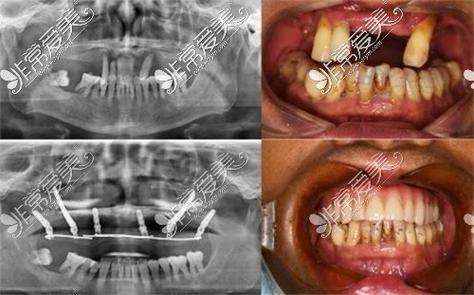

在诊疗特色上,医院以疑难种植牙和数字化矫正为两大技术支柱,同步发展儿童齿科、美学修复、牙周治疗等特色科室。其中,穿颧穿翼种植技术突破传统种植对牙槽骨条件的限制,成功为多位牙槽骨重度缺失患者实现“当天种牙当天用”;矫正团队由原公办医院正畸科医生领衔,采用隐适美、时代天使等数字化矫正系统,年均完成复杂错颌畸形病例超千例。

1. 疑难种植牙:针对牙槽骨重度萎缩、半口/全口牙缺失患者,开展穿颧种植、穿翼种植、即刻种植、上颌窦内外提升等复杂技术,结合数字化导板实现精细植入,患者当天即可戴临时牙冠进食。

穿颧穿翼种植牙技术是南京博韵口腔的核心竞争力之一,该技术突破传统种植对牙槽骨高度的限制,通过将种植体直接植入颧骨或翼板骨等高密度骨质区域,无需植骨即可实现半口/全口修复。以68岁的颜阿姨为例,其因长期牙缺失导致上颌骨重度吸收,传统种植需植骨且修复期长达6个月,经陈慧玲医生团队采用“双侧颧种植 + 穿翼种植”联合技术,仅植入6颗种植体便完成上半口固定修复,手术时间3小时,术后当天即可进食软食,3个月后更换恒久牙冠,咀嚼功能修复90%以上。